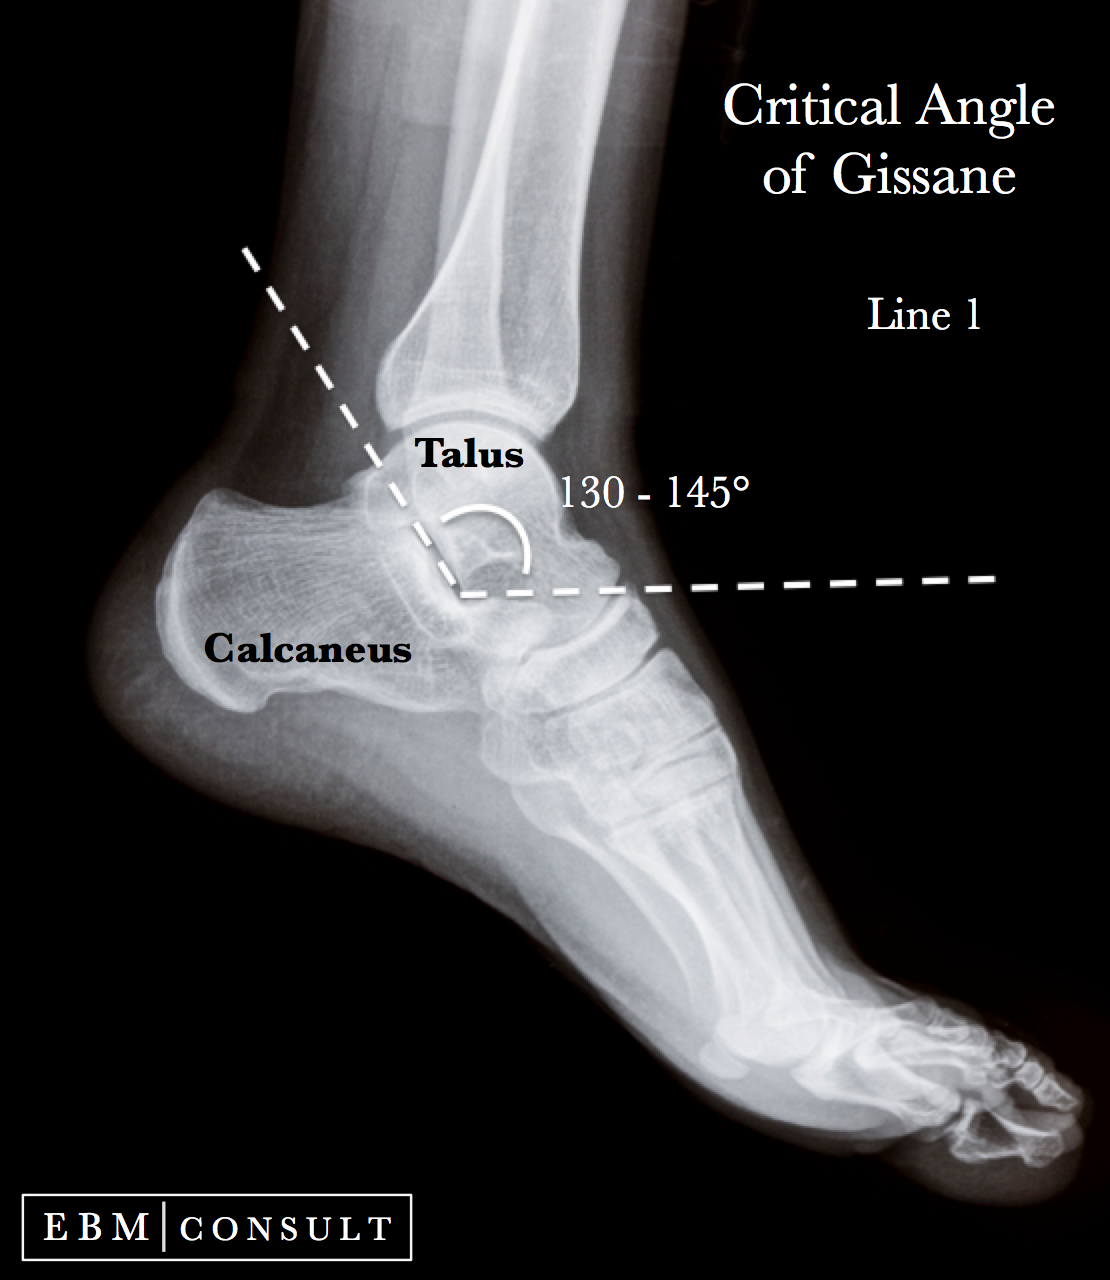

Anatomy Critical Angle of Gissane for Calcaneus Fractures

Anatomy Critical Angle of Gissane for Calcaneus Fractures Calcaneal Pitch Angle Radiology The calcaneal inclination or calcaneal pitch angle (angle c) is formed by the line connecting the most inferior part of the tuberosity of the. Compare to pes planus (figure 2). If < 20 degrees then pes planus. Foot collapse) can be distinguished from congenital pes planus by carefully assessing the. Angle formed by the horizontal and a line from the. Calcaneal Pitch Angle Radiology.